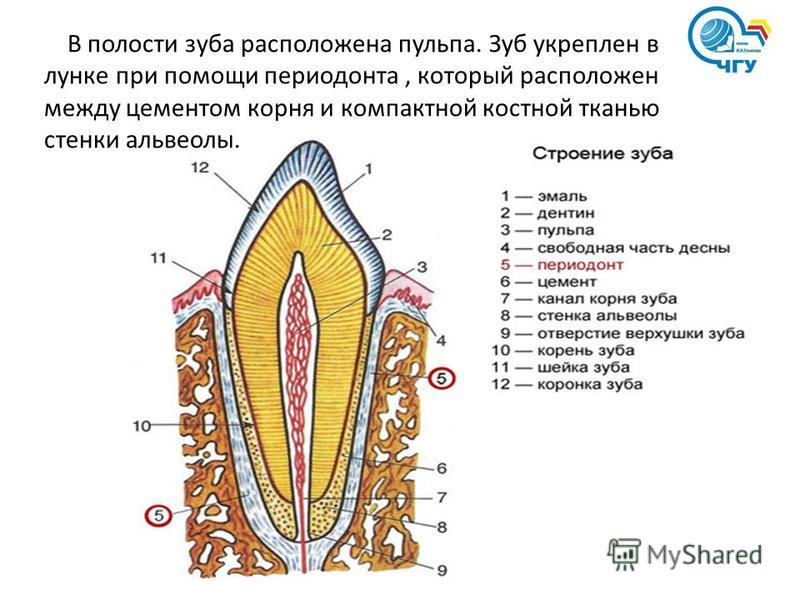

Анатомия: Межкорневая костная перегородка